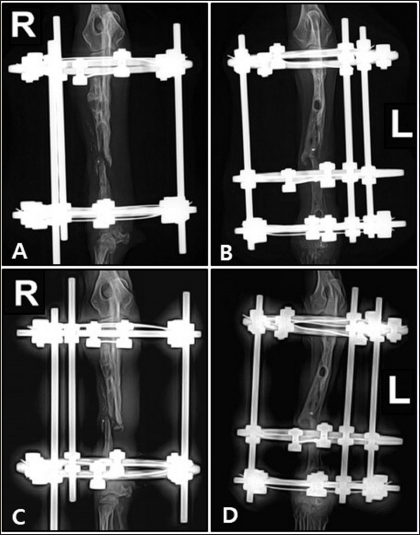

A two-step surgical plan was developed for managing the fractures. The remaining pin was removed in the first surgery and a CEF was applied for temporary fixation (Fig. 2A and B). Pins used included two 0.9 mm K-wires placed proximally and distally in a crossed manner, and one 1.2 mm olive wire placed in a single location. Anticipation of bone regeneration around areas of bone lysis near screw holes, and physical rehabilitation focused on inducing forelimb use until the second surgery. During the 6-week maintenance period of the temporary external fixation device, partial bone regeneration was observed in some areas of bone loss (Fig. 2C and D). Although forelimb ambulation remained plantigrade, there was an improvement in utilizing the limb smoothly with weight-bearing. In the second surgery, the CEF device was removed, and a surgical approach was made to apply the bone plate. The atrophied fracture sites on both sides showed no signs of bone regeneration and were partially debrided to expose the bone marrow cavities. The fracture was then fixed with a long bone plate and 1.5 mm screws. Autografts were harvested from the iliac wing and transplanted around the fracture site. This procedure was performed identically on both limbs with the fascia and skin closed in a standard manner. Additionally, CEF methods involved applying 0.9 mm K-wires, the same size as those used in the first surgery, above and below the plate on the fractured radius to provide further stability (Fig. 3).

Preoperative medications for both surgeries included tramadol (5 mg/kg, IV), cefazolin (30 mg/kg, IV), famotidine (0.5 mg/kg, IV), and midazolam (0.2 mg/kg, IV). General anesthesia was induced with propofol (5 mg/kg, IV) and maintained with 1.5%–2% isoflurane in oxygen. Intraoperative analgesia was provided by a constant-rate infusion of ketamine and lidocaine. The forelimbs were then prepared for routine aseptic surgery. The entire surgery lasted 2 hours and 50 minutes. Postoperatively, cefazolin was administered for 5 days, along with tramadol and meloxicam (0.1 mg/kg, SC) for pain management. Amoxicillin syrup was prescribed for an additional 3 weeks as an antibiotic. Sutures were removed in the second postoperative week, and ongoing physical rehabilitation was implemented. External fixation devices were removed in the fourth postoperative week. Radiographic assessments showed a union of the right radius by the eighth postoperative week and the left radius by the tenth postoperative week (Fig. 4). Although forelimb ambulation remained plantigrade, the dog’s overall gait improved, enabling consistent quadrupedal movement.

Fig. 3. Lateral radiograph of bilateral radius and ulna fracture reduced using circular external fixation along with plate and screw fixation.